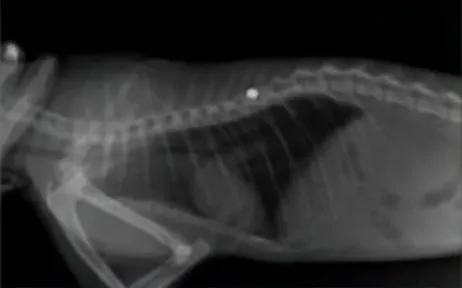

Al realizarle una placa, detectaron que el gato tenía una bala en su columna vertebral que le cortó la conexión y sensibilidad con sus patitas traseras, necesitando que le vacíen la vejiga.